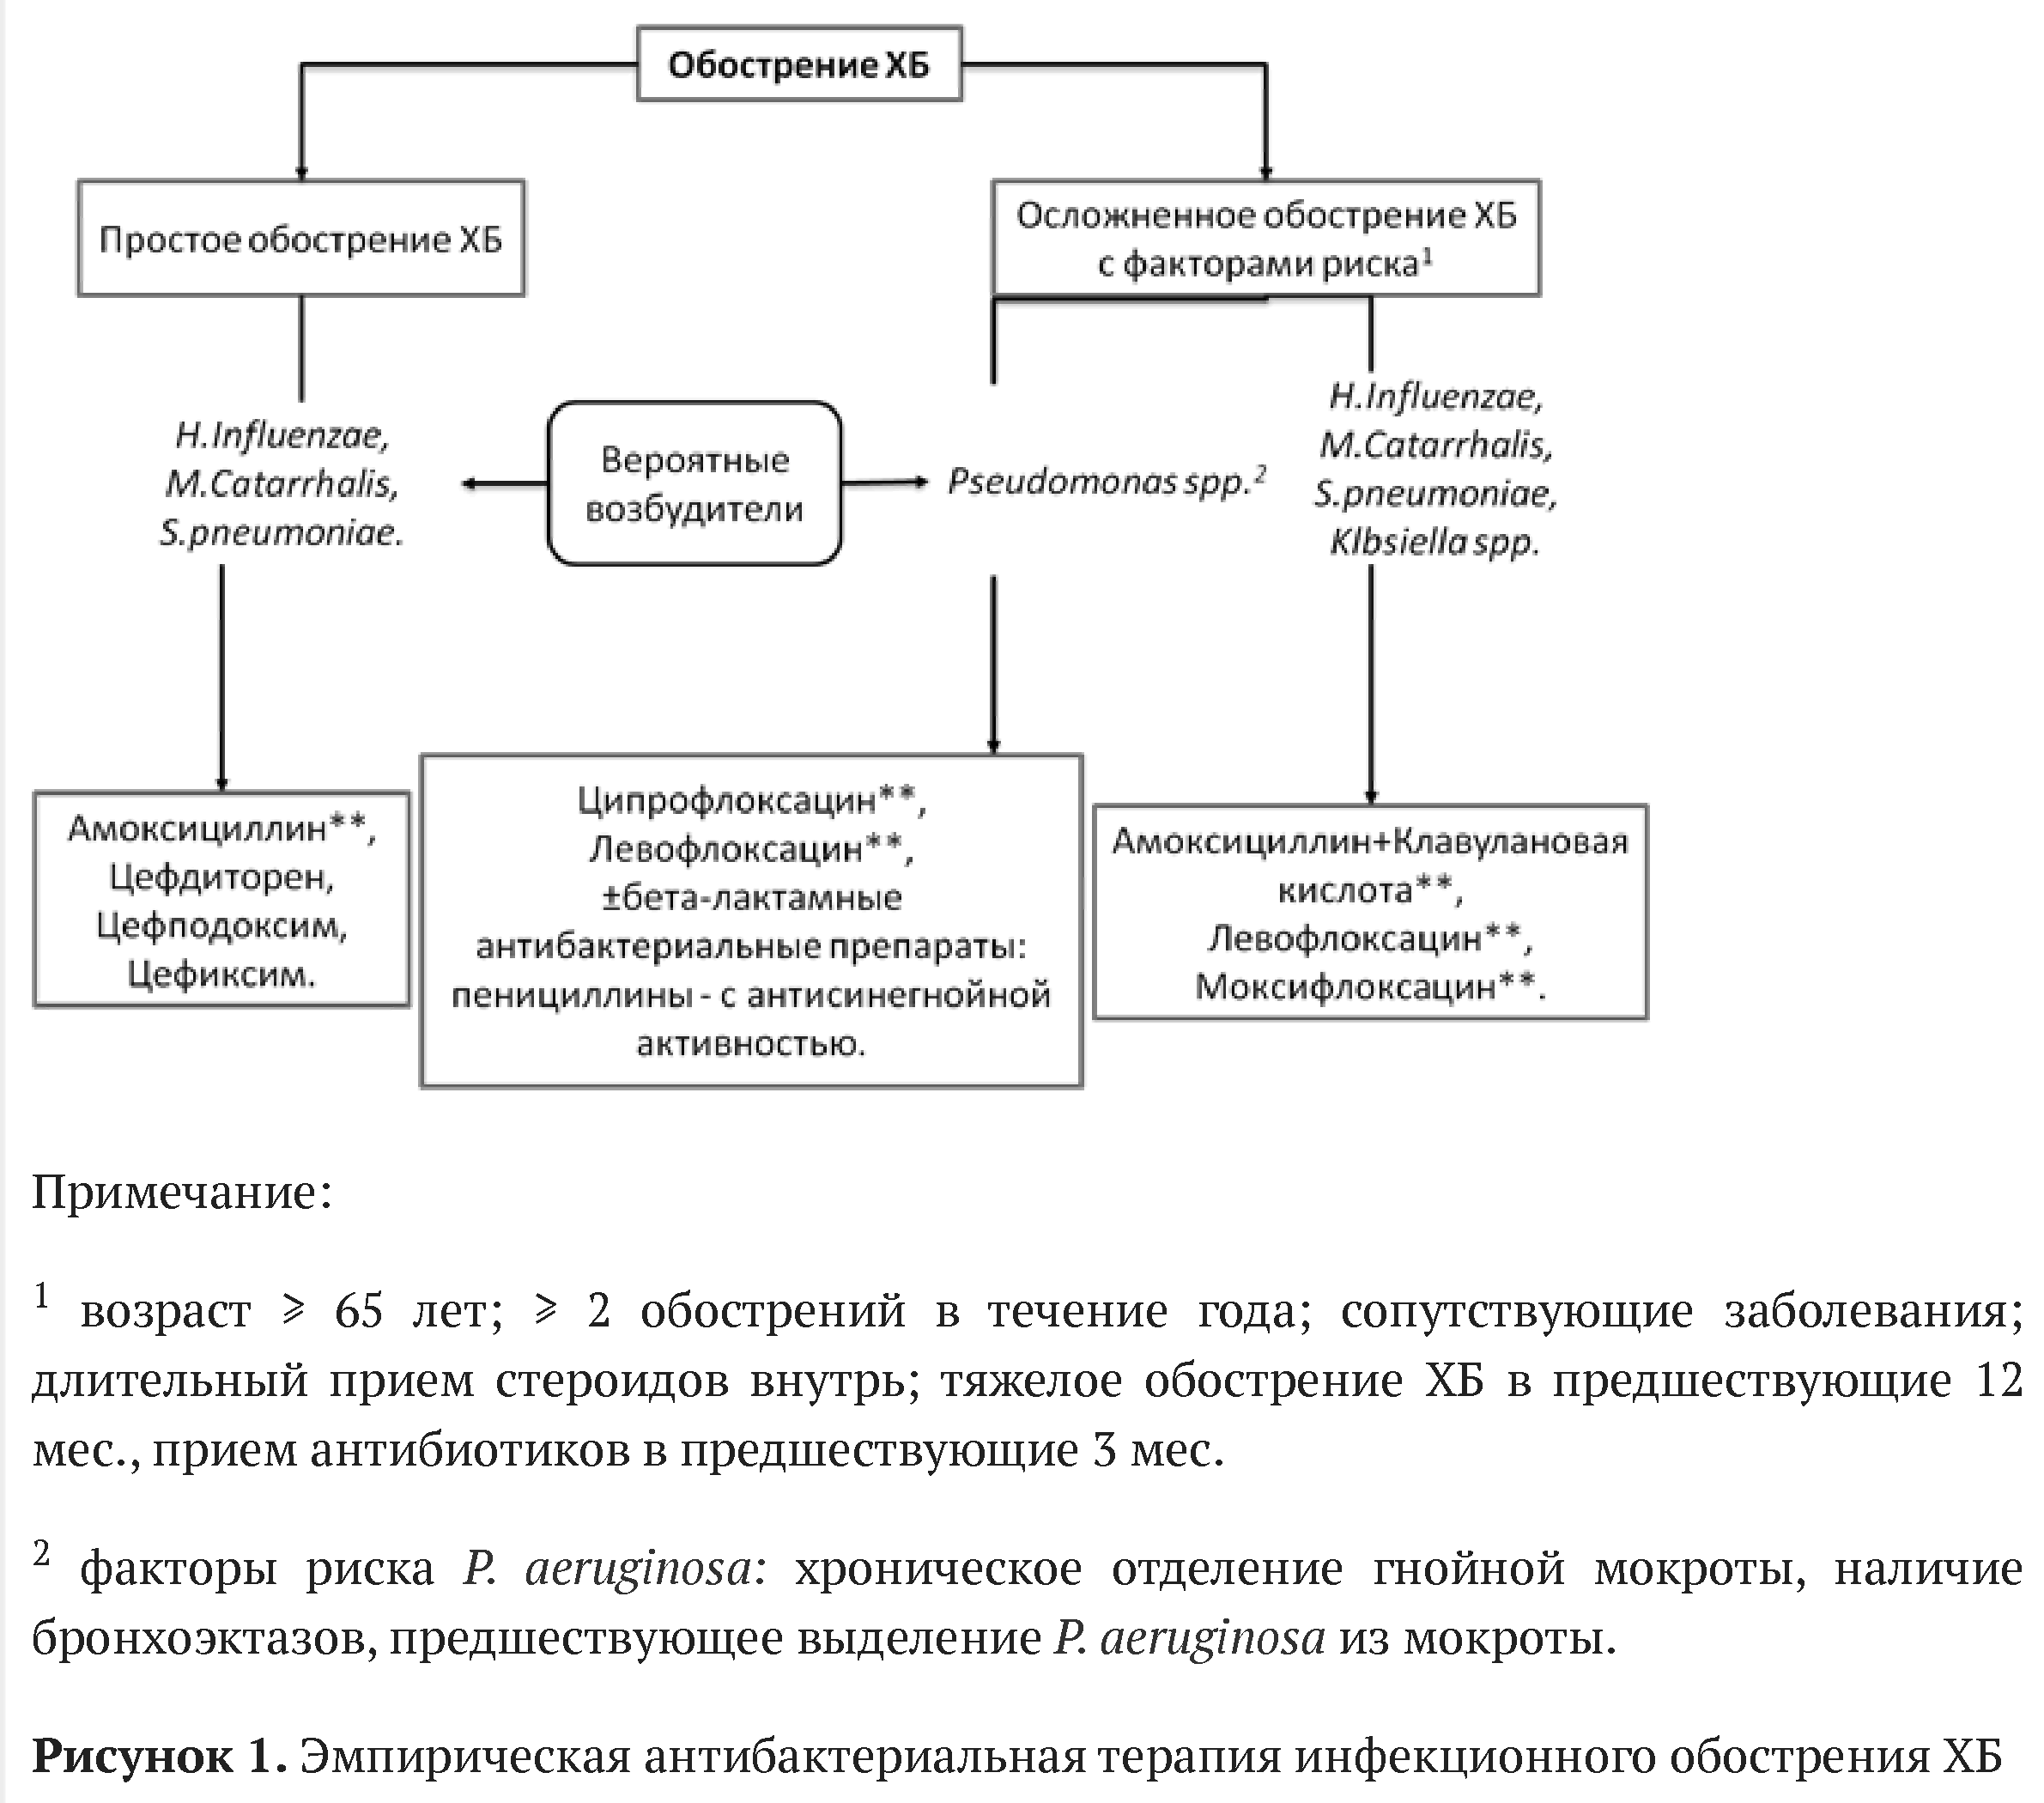

- Назначение антибактериальных препаратов рекомендуется у пациентов с I и II типами обострения ХБ по Anthonisen для лечения обострения ХБ с наибольшей эффективностью [27, 83].

Предполагаемый спектр респираторных патогенов, играющих этиологическую роль в обострении ХБ, и, соответственно, оказывающих влияние на выбор эмпирической антибактериальной терапии зависит от наличия факторов риска встречи с антибиотикорезистентными штаммами микроорганизмов и Pseudomonas aeruginosa.

Факт обнаружения Pseudomonas aeruginosa при микробиологическом исследовании мокроты не характерен для ХБ, а может свидетельствовать об инфицированной бронхоэктазии.

Факторы риска осложнённого обострения ХБ:

- возраст  лет,

лет,

- сопутствующие заболевания (сахарный диабет, застойная сердечная недостаточность, заболевания печения и почек с нарушениями их функции, алкоголизм),

- частые инфекционные обострения ( в год),

в год),

- тяжелое обострении ХБ в предшествующие 12 мес.,

- прием противомикробных препаратов системного действия более 2 дней в предшествующие 3 мес.

Предикторы инфекции P.aeruginosa:

- частые курсы антибиотиков (>4 за год);

- выделение P.aeruginosa в предыдущие обострения,

- частые курсы кортикостероидов системного действия (>10 мг преднизолона** в последние 2 недели);

- инфицированная бронхоэктазия.

- При обострении ХБ у пациентов без факторов риска рекомендуется назначение амоксициллина** или пероральных цефалоспоринов III поколения (цефдиторен, цефподоксим, цефиксим) (см. рис. 1) для лечения обострения ХБ с наибольшей эффективностью [52-54].

Уровень убедительности рекомендаций В (уровень достоверности доказательств 1)

Применение комбинации пенициллинов, включая комбинации с ингибиторами бета-лактамаз, или "респираторных" фторхинолонов (моксифлоксацин**, левофлоксацин**) рекомендуется следующей категории пациентов с обострением ХБ с соответствующими критериями назначения антибактериальной терапии по Anthonisen [55-58]:

- возраст пациента  лет;

лет;

- тяжелые сопутствующие заболевания (сахарный диабет, застойная сердечная недостаточность, заболевания печени и почек с нарушениями их функции и др.);

-  обострений в течение года, потребовавшие госпитализации;

обострений в течение года, потребовавшие госпитализации;

- применение кортикостероидов системного действия или антибиотиков в предшествующие 3 мес.

Уровень убедительности рекомендаций В (уровень достоверности доказательств 1)

Комментарии: Оптимальная продолжительность антимикробной терапии при обострении ХБ составляет 5-7 суток [59-62].